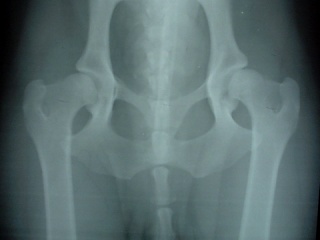

ベルの股関節(1999/12/15)